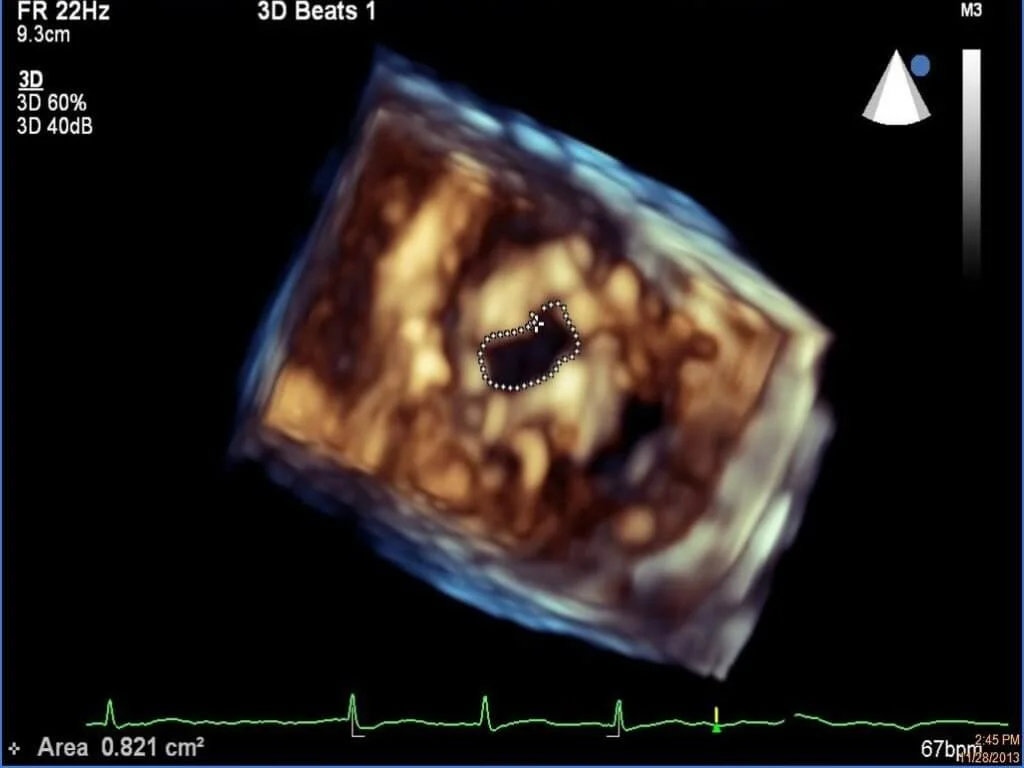

近年,3D心臟超聲波是房顫診斷發展的新領域。雖然心臟超聲波本身不是用作診斷房顫,而是顯示心臟結構的一種檢查方法,卻可用於評估患有房顫病人的中風風險。黃醫生解釋:「心臟超聲波主要是看心臟的結構及心臟瓣膜的功能,可以看到有沒有心臟發大、冠心病等迹象。如果高血壓患者,病情控制得不好,心臟肌肉就會增厚,這些資料有助評估病人是否有增加中風的因素。」心臟超聲波另一檢查要點是判斷房顫的心臟結構性問題,例如二尖瓣狹窄,從而決定房顫患者日後採用什麼治療方法。

黃醫生表示,3D心臟超聲波技術更應用於左心耳封堵手術。利用3D打印技術,量身訂造患者的心臟結構模型,能為需要以左心耳封堵手術治療的房顫患者,提供更有成效的術前規劃。